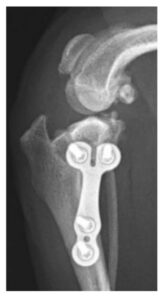

症例2. 膝蓋骨内方脱臼併発症例に対してTPLO-Mを実施した症例(12歳、チワワ、3 kg)

TPLO-M(TPLO-medialization)とは、膝蓋骨内方脱臼を伴う前十字靭帯断裂の犬において、

TPLOに脛骨粗面転移術を併用するのではなく、TPLOの脛骨近位骨片を内側に移動させることで、膝関節伸展機構のアライメントを整復する方法です。

| 治療前(側方像) | 治療後(側方像) | 治療前(前後像) | 治療後(前後像) |